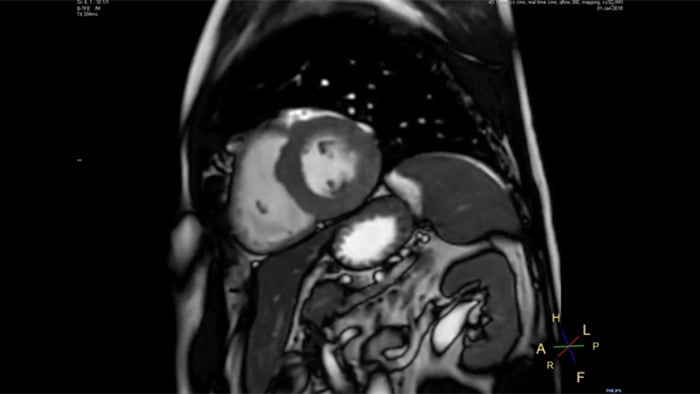

4.8 sec breath hold time

Since short breath hold times make it easier for our patients to comply, the failure of breath holding largely disappeared.

At our facility, we found in Cardiac MR fewer breath holds are now needed, or breath hold times are shortened."

Dr. Takashi Koyama, MD, PhD, Diagnostic Radiologist and Director of the Department of Radiology Center and Diagnostic Radiology, Kurashiki Central Hospital, Japan

A 15- or 16-second breath-hold is tough for many cardiac patients. With Compressed SENSE we actually have protocols now that can get that below 10 seconds. It’s a lot easier to get through for a patient, and patients are a lot more satisfied with the experience.”

Trevor Andrews, Ph.D., MR Physicist, University of Vermont Medical Center, USA

The MRI staff at Kurashiki Central Hospital incorporated Compressed SENSE into most of the brain, spine, abdominal, and cardiac examination protocols on their Ingenia 1.5T, resulting in fast and high-quality MRI scans, which is welcomed by patients and staff.